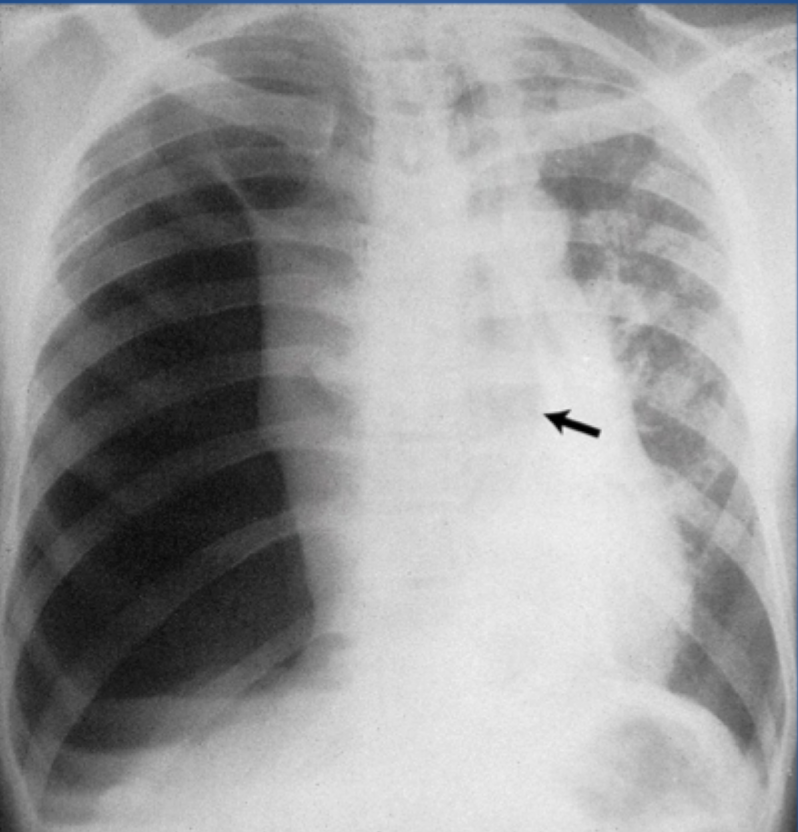

Q

?

A

Tension pneumothorax:

-Large amount of air in the affected hemithorax and CONTRALATERAL shift of the mediastinum